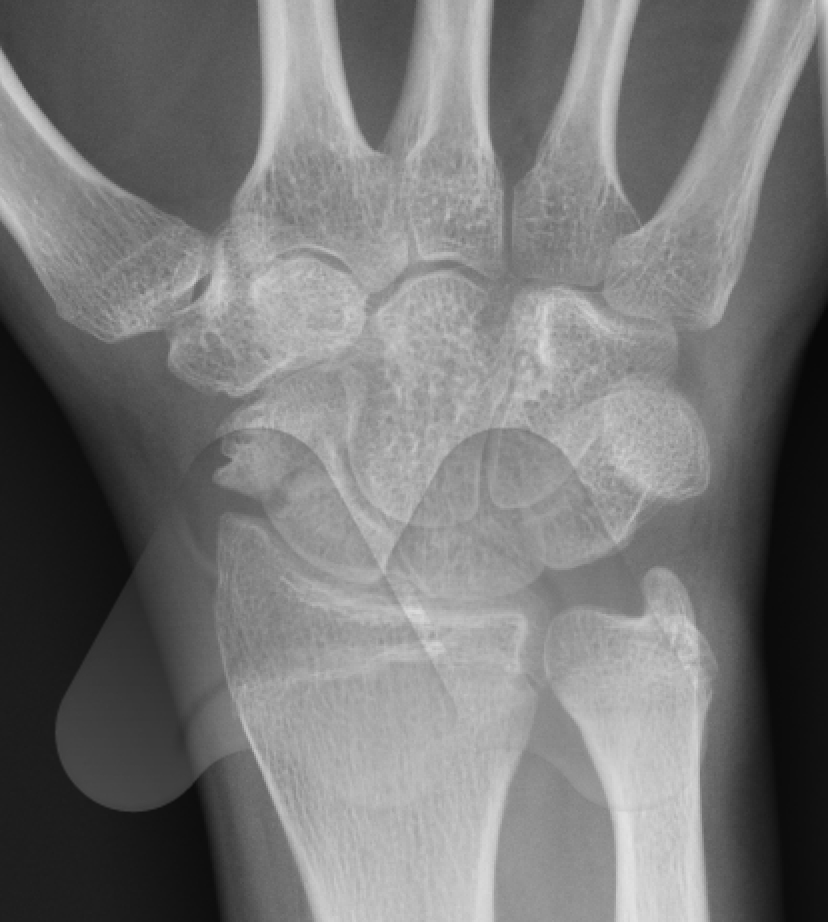

The Scaphoid is one of the eight carpal bones that make up the wrist. It is the commonest carpal bone to be fractured and is more common in young men. The injury occurs often from a fall onto an outstretched hand, sports related injury or a sudden torque injury from power tools. Scaphoid fractures tend to cause swelling and pain on the radial (thumb) side of the wrist and can often be overlooked as a wrist sprain. Despite seeking medical attention, there is a high rate of missed diagnoses due to many fractures not easily seen on initial X-Ray. The scaphoid has an unusual blood supply which can affect it’s healing. It is the key bone that stabilises the wrist and if a fracture is missed or does not heal, this can lead to collapse and arthritis in the wrist at an early age. If you have pain on the radial side of the wrist following an injury that continues for longer than a week, you should seek medical attention.

If initial X-Rays do not show the fracture but there is persistent pain and swelling in the radial side of the wrist, your doctor may ask you to have a CT or MRI scan to give more detailed imaging of the area. This can identify occult scaphoid fractures and the amount of displacement or other injured structures in the area such as distal radius fractures, scapholunate ligament injuries, trapezium fractures or other ligamentous injuries. This helps guide you and your doctor’s choice of treatment.